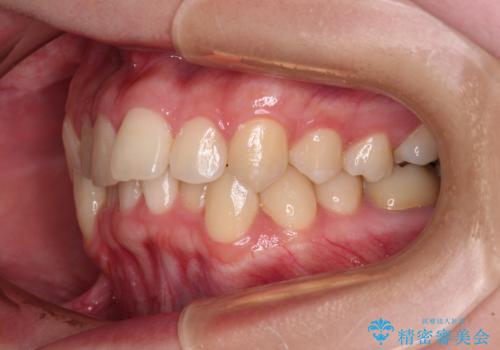

前歯のクロスバイト ギラギラのワイヤー装置で矯正治療

- 前歯のクロスバイトを改善したいとのことで来院された患者様です。

マウスピース矯正では前歯の神経への負担が大きいことを懸念され、ワイヤー装置による矯正治療を行うこととしました。

クロスバイトが改善する際は、前歯しか接触しないため、痛みがあったり食事が取りにくかったりと、不便な時期がありますが、1年強の短期間で無事に治療を終えることができました。